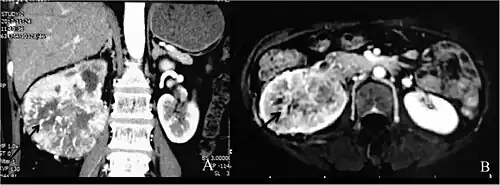

Individuals with Dioctophyme renale infection (known as dioctophymosis) typically present with unspecific symptoms including hematuria[1][3] (blood in urine), nephritis, loin pain,[7] renal enlargement, and/or renal colic[1] (intermittent pain in the kidney area), which may result from the rare migration of worms through ureters.[5][7][1][3] In some cases the fibrosis occurring after parasite infection is an incidental finding in ultrasound or CT scan, mimicking renal cancer, leading to radical nephrectomy.[11]